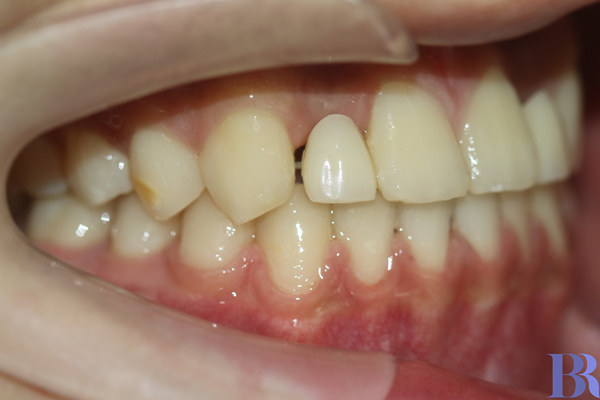

교정 전 오른쪽 모습

반대교합 양상이 심한 것을

알 수 있습니다.

과연 교정으로만 해결할 수

있을까 싶을 정도입니다.